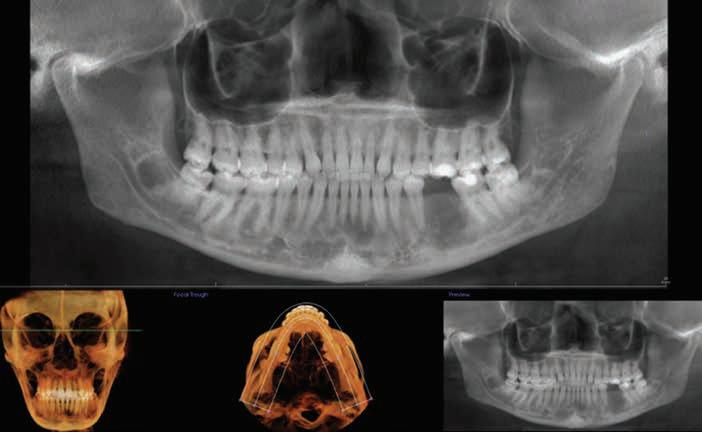

Cone-Beam Computed Tomography

Cone-beam computed tomography (CBCT) has become an essential tool in the field of dentistry, as it offers a highquality, 3-dimensional (3D) image.25 It is superior to bone sounding and conventional 2-dimensional radiography in the assessment of CEJ and bone morphology, as well as detecting abnormal root anatomy and bony dehiscence or fenestrations.13 Furthermore, it is more comfortable for patients and less invasive than bone sounding.26 Leung and colleagues reported on the greater accuracy of CBCT in identifying the CEJ than identifying alveolar bone margin.26 This was due to the fact that the CEJ is the junction between enamel and cementum, which have different densities, and the latter is the interface between cementum and bone, which have similar densities. In addition, greater accuracy was reported in detecting bone fenestration than dehiscence.

Grimard and colleagues reported a strong correlation between CBCT and direct surgical measurements of the hard tissues.27 Although CBCT was found to underestimate the distance from CEJ to the base of bone defect, it precisely estimated the distance between CEJ and alveolar crest. In contrast, intraoral PA radiographs were found to be less reliable than CBCT, as they underestimated the measurements of all investigated parameters considerably.27 Batista and colleagues suggested the use of CBCT for the diagnosis and presurgical planning of APE cases, as it provides accurate measurements related to the CEJ and alveolar bone crest, in addition to the actual anatomic crown length.4

The use of a digital workflow to treat patients with APE has been proposed in situations with restorative treatments, as well as when no restorative treatment is anticipated.38,39 In this method, a CBCT scan is acquired to analyze the level of the alveolar bone crest in relation to the CEJ. An intraoral scan is acquired to aid in fabricating a surgical guide. Digital Imaging and Communications in Medicine files obtained from the CBCT are converted to Standard Tessellation Language format and then superimposed with Standard Tessellation Language files acquired from the intraoral scan. The level of the CEJ is then marked (Figure 5) to guide the gingivectomy incision line, followed by a second line 3 mm apical to the CEJ line to guide the bone resection.

Figure 5. After superimposition of the cone-beam computed tomographic scan and intraoral scan, the cementoenamel junction and future bone level are marked. Reproduced from Alhumaidan A, Alqahtani A, al-Qarni F. 3D-printed surgical guide for crown lengthening based on cone beam computed tomography measurements: a clinical report with 6 months follow up. Appl. Sci. 2020;10(16):5697, CC-BY 4.0. https://doi. org/10.3390/app10165697.39